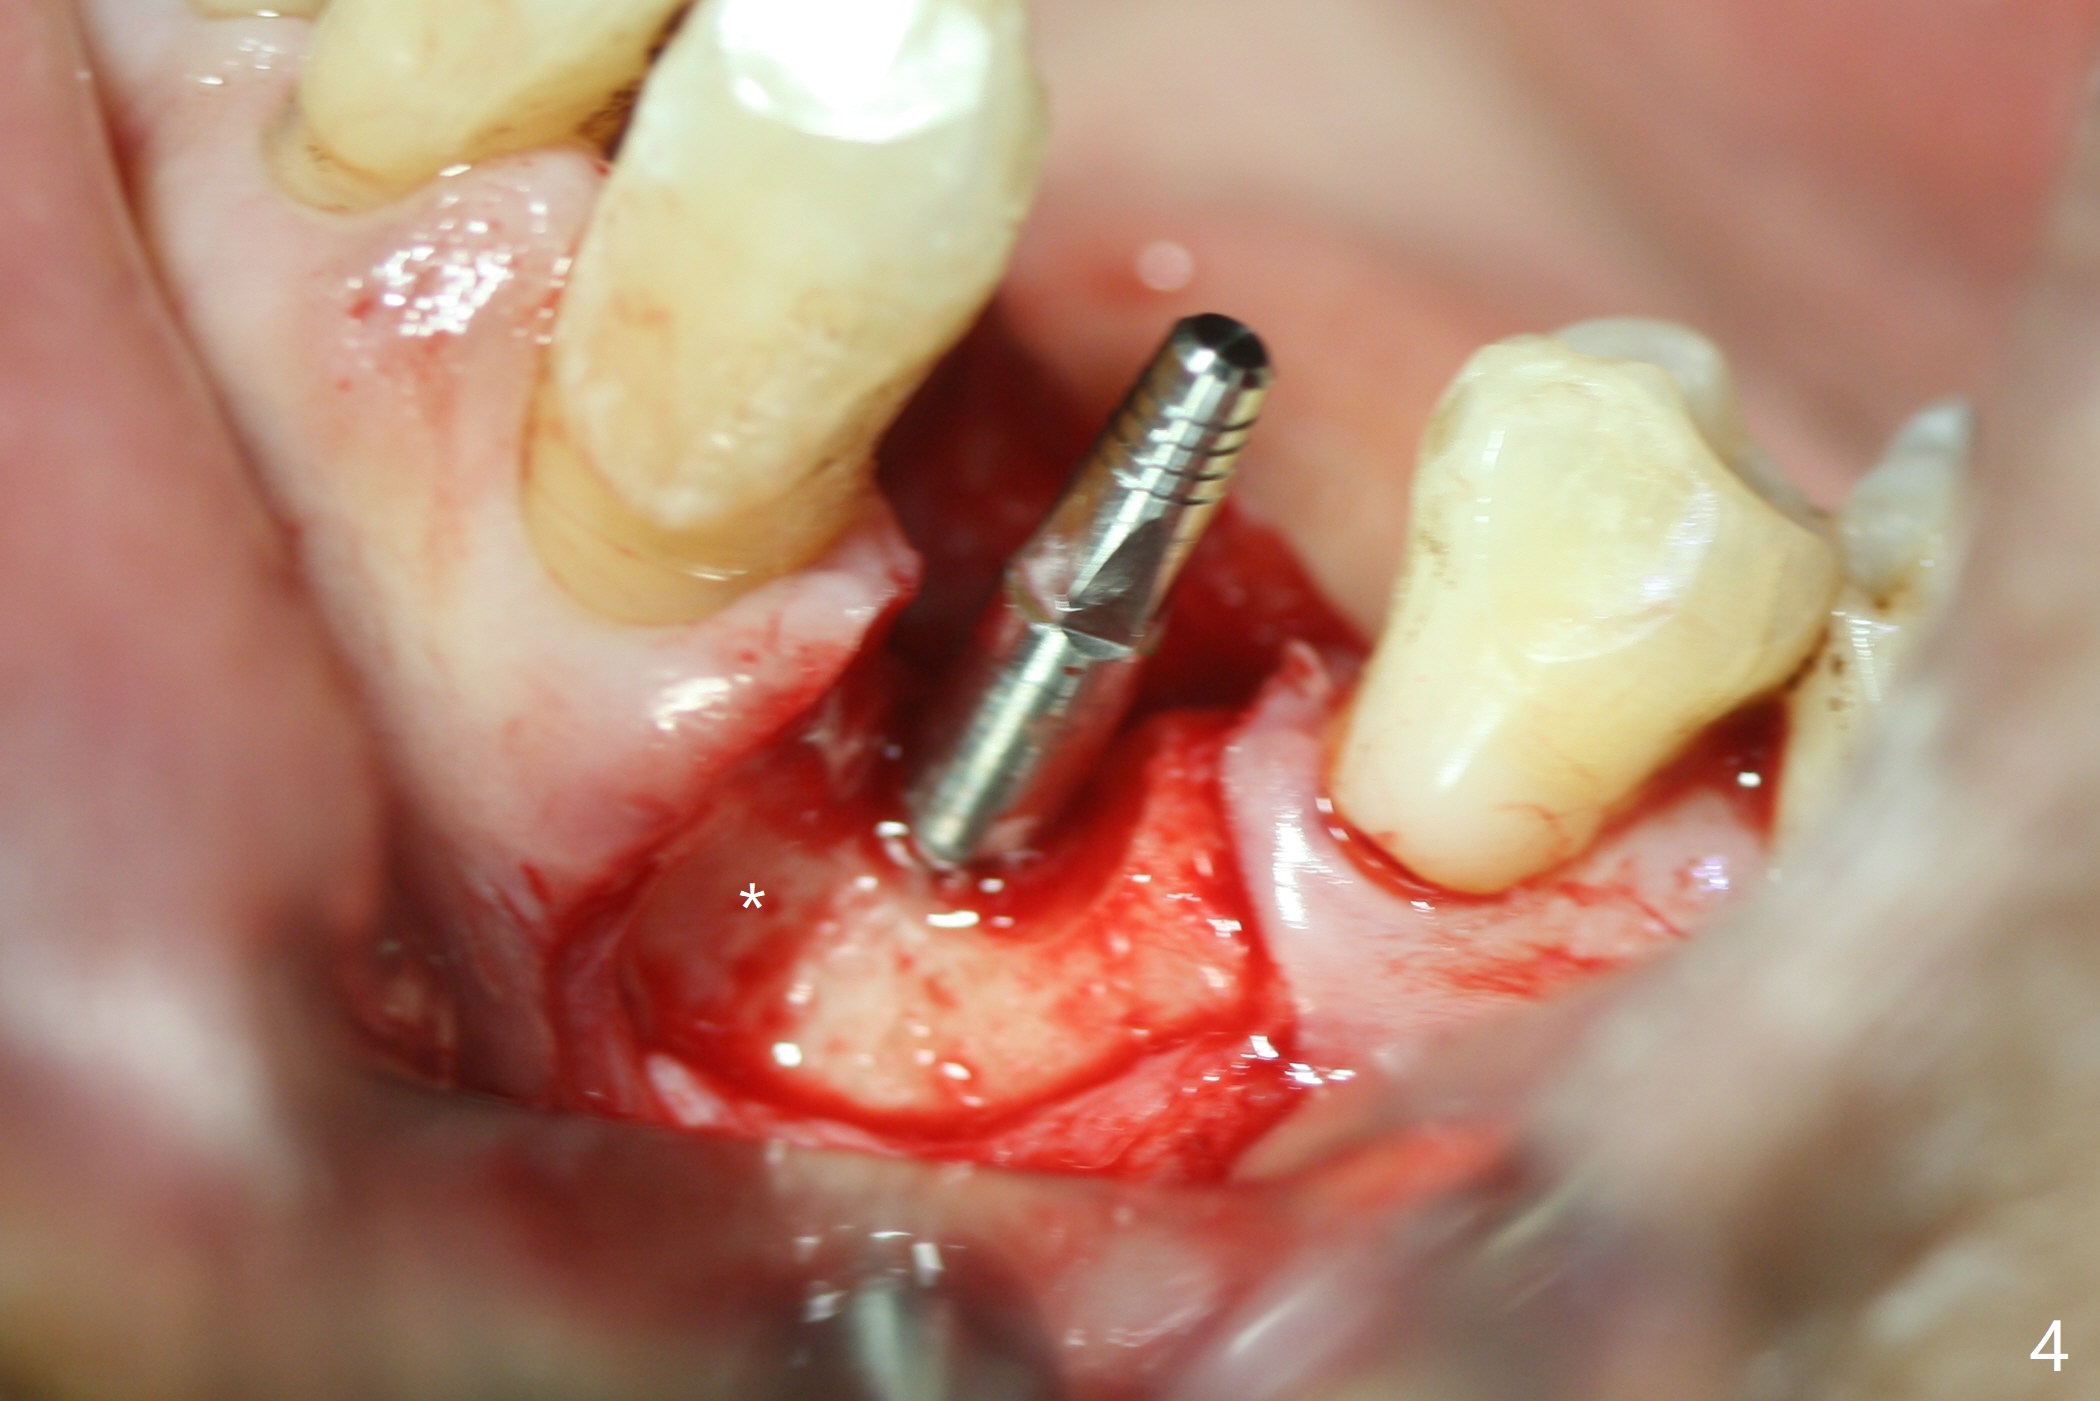

After incision at #21 (Fig.1) and flap elevation, the narrow ridge is reduced and initial osteotomy is made (Fig.2,3). Following moving the osteotomy distal, a 3x12(4) mm 1-piece implant is placed with >35 Ncm (Fig.4-6). Vanilla Graft is placed in the most concave buccal defect (Fig.1,4 *) and over the ridge reduction area (Fig.6 *). No bone loss is observed 3 months postop (Fig.7).